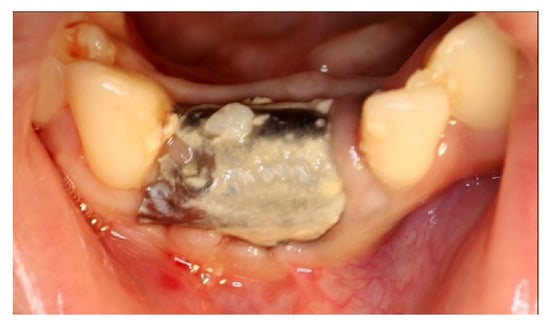

Following a full-thickness flap, three incisors (4.2, 4.1 and 3.1) were extracted (Figure 13b). After a careful curettage of the cyst cavity, collagen sponges were grafted in the cavity. The collagen sponges were wet with surgical site blood (Figure 14a). A titanium foil (Figure 14b) was shaped and positioned and the flap sutured.

Figure 14.

(a) Extraction site filled with collagen sponges; (b) titanium foil and suture.

At the follow-up, a significant plaque accumulation on the foil surface was observed; nevertheless, there were no significant signs of soft tissue distress (Figure 15).

Figure 15.

Accumulation of plaque on the foil.

4 months after the surgery, the barrier was withdrawn and, behind it, growth of elastic and thick osteoid tissue was observed (Figure 16a,b). After further 4 months, a CBCT was performed, and the amount of regenerated bone was observed (Figure 17a–d).

Figure 16.

(a) Removal of titanium foil after 4 months; (b) osteoid tissue with hard but still elastic consistency covered by not-epithelized mucosa.